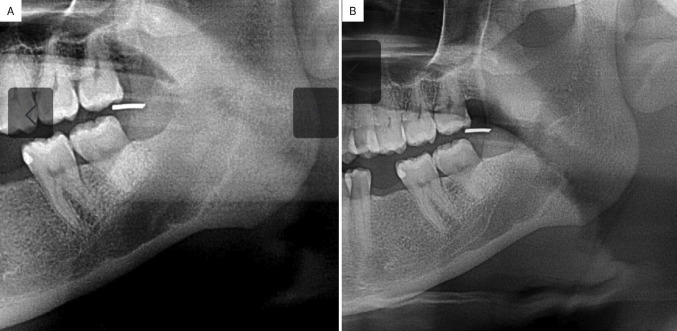

Myofibroma (MF) is an uncommon benign mesenchymal neoplasm composed of myofibroblasts. Traumatic neuroma (TN) is a non-neoplastic proliferative disorder of the nerve sheath in response to injury or surgery. Both are uncommon in the jaws. We present a case of a 39-year-old Afro-descendant woman with a unilocular radiolucent lesion in the posterior mandible, showing mild expansion and cortical disruption. Biopsy revealed proliferation of fascicularly arranged spindle cells strongly positive for α-SMA and podoplanin, with low Ki-67 (<5%), and the final diagnosis was central MF. Ten months after enucleation and curettage, persistent pain led to a second biopsy, which revealed proliferation of multiple hyperplastic nerve fascicles consistent with TN. The postoperative course was uneventful with 14-month follow-up. A discussion on the clinicopathological criteria for differential diagnosis of MF and other spindle cell tumors as well as the rare occurrence of post-surgical TN is also provided. Key words:Mouth neoplasms, differential diagnosis, mandible, oral pathology.